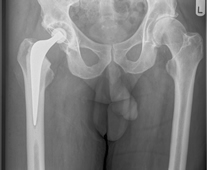

X-Ray showing a Right Total Hip Replacement. This is a reverse hybrid hip replacement, with a cemented highly cross linked polyethylene cup (Reflection™) and an uncemented femoral stem (Polar stem™). Enlarge